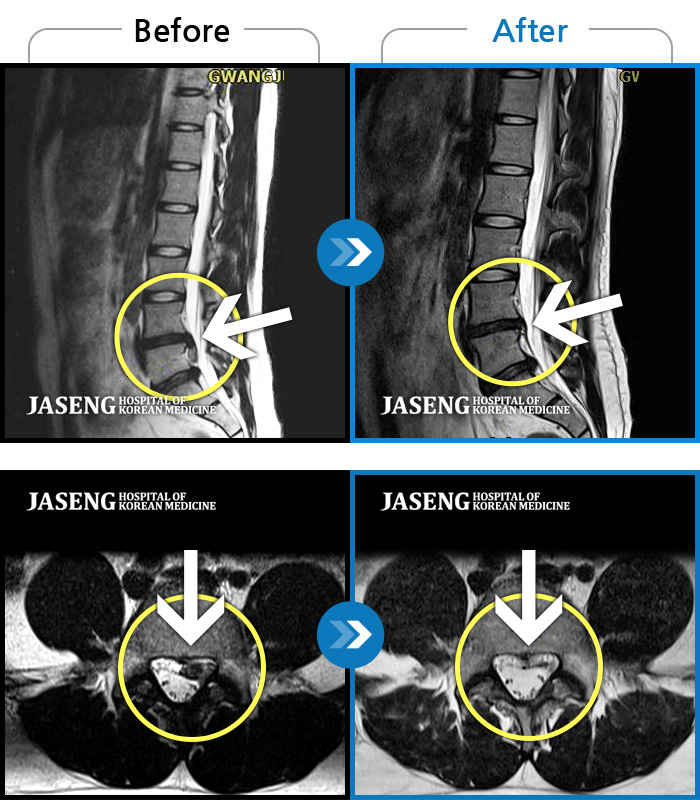

MRI로 보는 치료결과

1,169건의 MRI 전후 사진으로

터진 디스크 흡수 사례를 확인하세요.

[촬영시기:24.03.30~24.11.11]

[촬영시기:24.03.30~24.11.11]

[해운대_허리디스크] 왼쪽 허리와 종아리가 저리고 발 감각이 둔해졌어요.조회수 0 2024.11.21 -